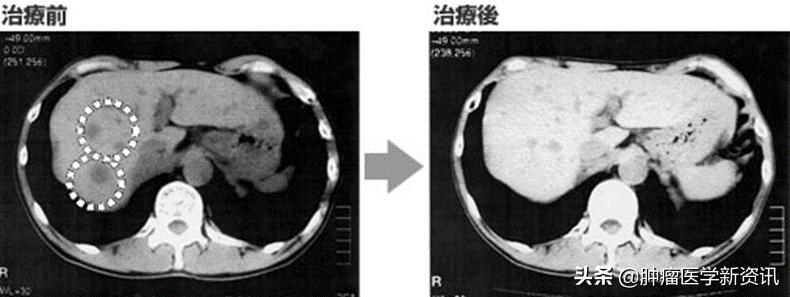

2. 一位59岁胰腺体尾癌男性患者在手术切除后进行抗癌药物治疗,但出现了肝脏转移,肿瘤标志物升高,后因强副作用停用抗癌药物。该名患者接受了日本免疫细胞治疗,三个月后CT检查肝转移灶已消失。后持续接受日本免疫细胞治疗防复发,经检查显示肿瘤标志物并无上升,肝转移灶也无复发,并持续维稳8年(如下图)。